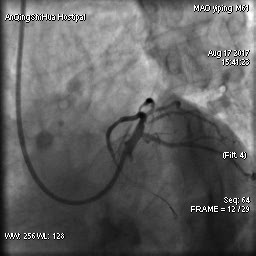

由于毛先生的病變涉及主干分叉,即復(fù)雜的真性分叉病變,為保證分支開口得到良好的開放,術(shù)者采取了操作復(fù)雜的雙支架術(shù)式,先后運(yùn)用掏支架網(wǎng)眼、球囊擴(kuò)張、雙球囊對吻擴(kuò)張、POT技術(shù)等,實(shí)現(xiàn)了完全血運(yùn)重建。術(shù)后,毛先生的嚴(yán)重心絞痛終得緩解。

術(shù)后 心臟左主干末端狹窄解除,血流通暢